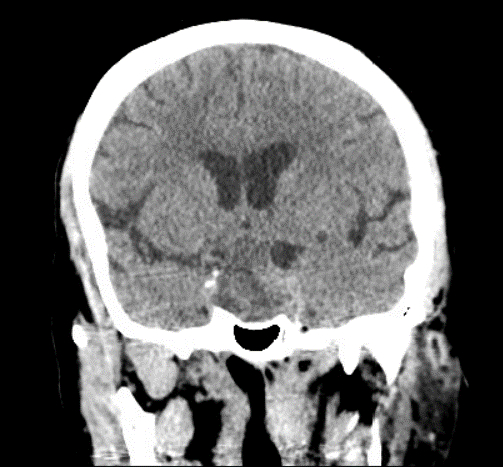

Case Presentation: We present a 49-year-old man with a known macroadenoma and a new diagnosis of type 2 diabetes mellitus who was admitted to the medical intensive care unit for severe diabetic ketoacidosis. He developed sudden onset left lower face and left arm weakness with dense left-sided neglect. His symptoms resolved when placed in Trendelenburg and given a fluid bolus. CT angiogram of the brain demonstrated a stenosed right distal internal carotid artery (ICA)/proximal M1 with a mixed-appearing attenuation inside the macroadenoma. CT perfusion demonstrated a large penumbra mismatch in the right MCA territory with no core volume.